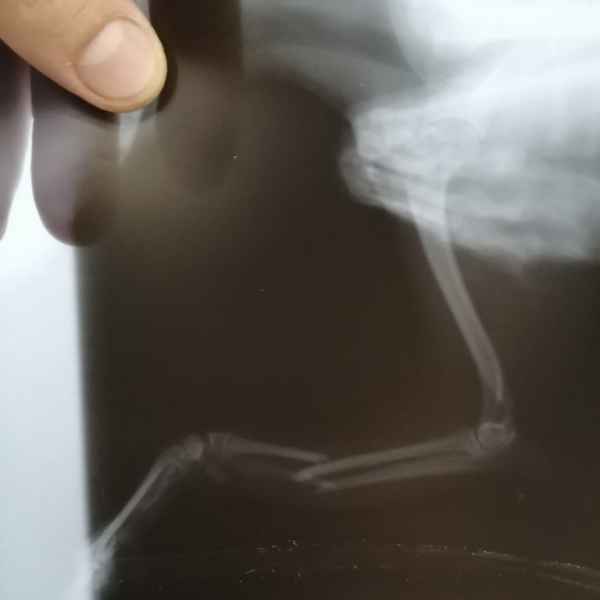

Вот что значит неудачно спрыгнуть с дивана. Это рентгеновские снимки одного из наших пациентов. Сначала хозяева обратили внимание на хромоту, а потом поняли, что у питомца очень болит лапа. Ещё бы не болело - поперечный перелом костей предплечья. Операция, установка DCP-пластины, восстановление, и он снова активный и жизнерадостный.

Этот пациент поступил к нам с кусаной раной левой грудной конечности После рентгенологического исследования обнаружили перелом костей предплечья. Сложность операции заключалось в том, что дистальный отросток лучевой кости был очень коротким. Хирургом нашей клиники было принято решение установить блокируемую lcp пластину. В данный момент пациент полностью восстановился..